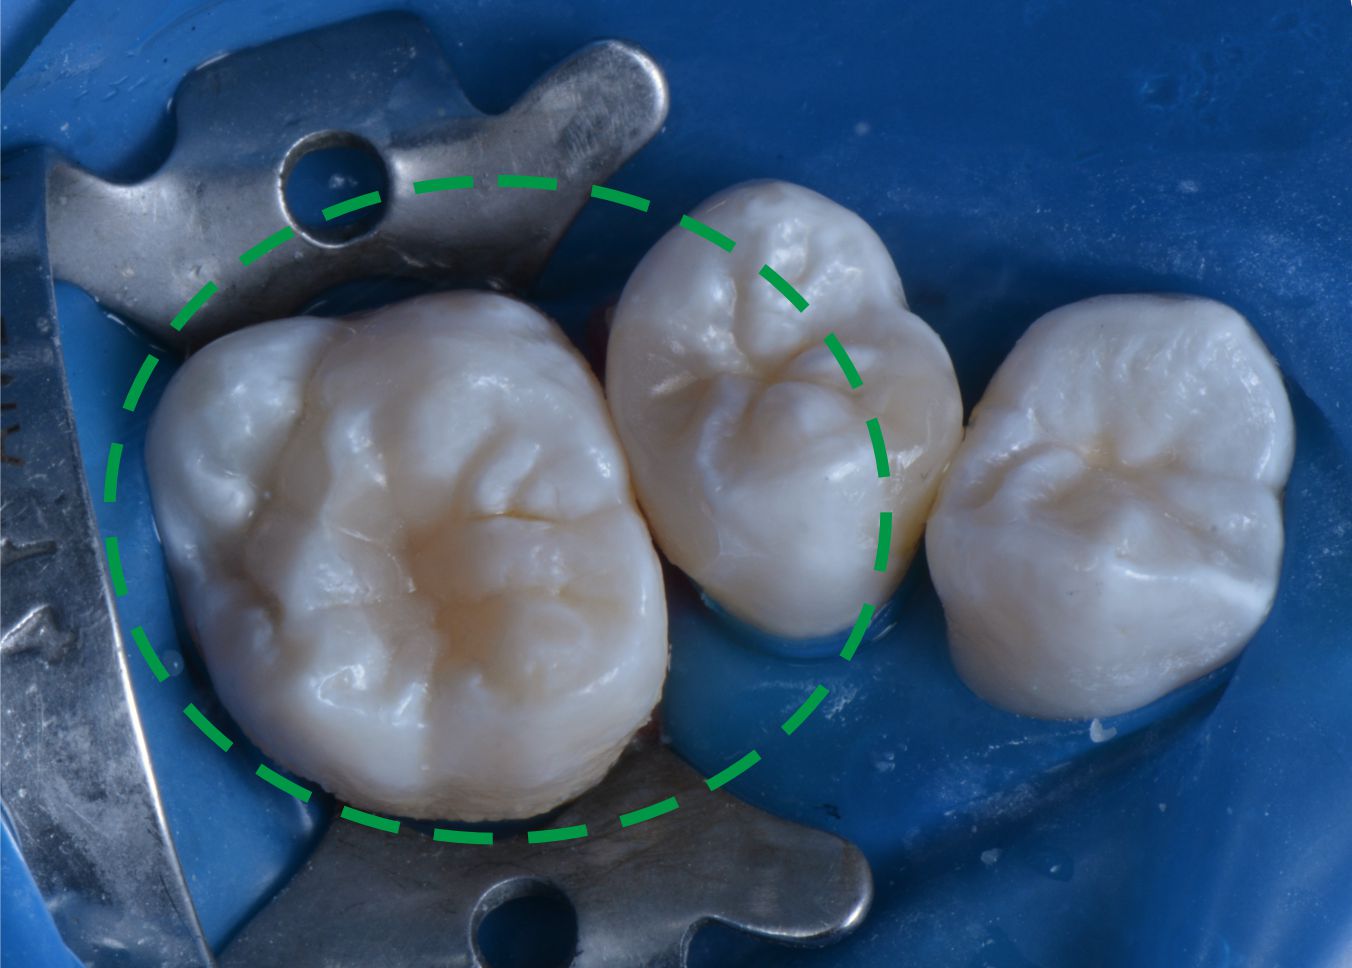

Лечение кариеса и восстановление формы зуба - просто шедевральная работа. Все никак не налюбуюсь своим зубом, уж очень красивый!! Спасибо!!!

Непростая ситуация, связанная с расположением зубов: лечение кариеса до начала ортодонтического лечения проведено максимально эффективно. Профессионалы своего дела!